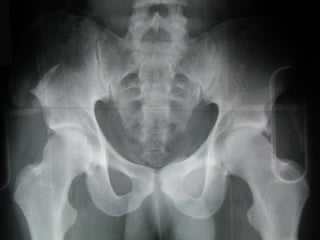

Anatomy of Pelvis

 Pelvis = sacrum + 2 inominate

bones

 Inominate bones = ilium,

ischium, pubis

 Pelvis contains one pair of fused

bone

 Each half contains: ilium, pubis,

and ischium

 Joined together in posterior by

sacrum

 Joined in anterior by symphysis

pubis

 Coalesce at triradiate cartilage.

 Ilium, ishium and pubis have three

separate ossification centers that

fuse at sixteen years.

 Gap in symphysis < 5 mm

 SI joint 2-4 mm